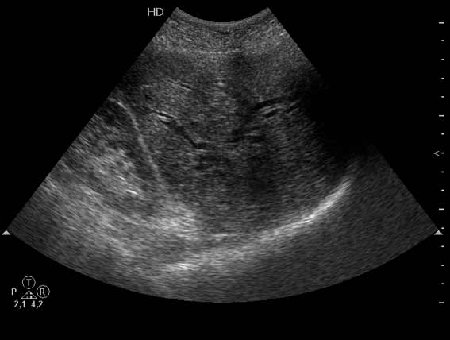

Не могу сказать что я вижу камень в холедохе на представленных сонограммах. Холедох расширен; интра-печёночные жёлчные пути тоже (значит прошло > 3 недель от момента обструкции). Жалоб на сильные приступообразные боли я не прочёл. Всё таки буду думать сначала о опухоли (если при УЗИ не нашли камня); рекомендация-таргетное КТ печени и поджелудочной.

Дело в том, что в холедохе имеется нечто изоэхогенное (не знаю, видно ли это нечто на ваших мониторах). Врач УЗИ при осмотре перед поступлением в стационар на основании этой картины в заключении отметил возможность опухоли холедоха.

Гнойный холангит на фоне обструкции БДС конкрементом (камень вне скана). В холедохе определяется желчь с осадком, которая может быть ошибочно принята за его опухоль.